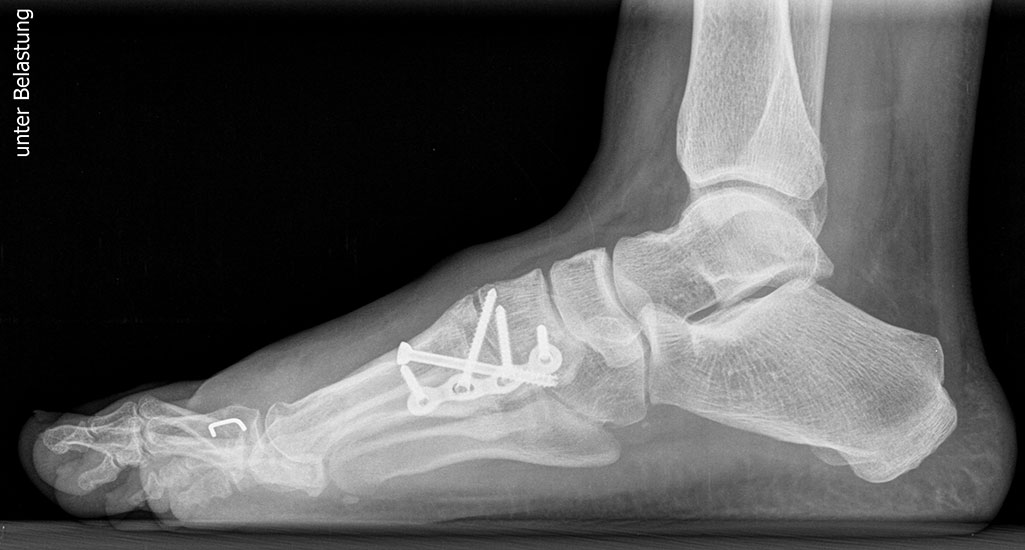

Bezüglich der Operationstechniken wird von früher häufig durchgeführten alleinigen Weich­teileingriffen am Großzehengrundgelenk aufgrund hoher Rezidivraten abgeraten 15. Die Operation nach Mc Bride mit lateralem Release, Exzision des lateralen Sesambeins, Abtragen der Pseudoexostose, Sehnenetransfer des M. adductor hallucis und mediale Kapselraffung zeigte unbefriedigende Mittel- und Langzeitergebnisse 16. Die Cerclage fibreux (mediale Kapselraffung) und das laterale Kapselrelease wird heute in Kombination mit einem knöchernen Eingriff angewendet. Bezüglich des Einsatzes von minimalinvasiven Operations­techniken vor Wachstumsabschluss liegen bisher keine Daten vor. Alle Osteotomien lassen sich nach Bedarf miteinander kombinieren. Es ist darauf zu achten, dass Osteotomien keine offenen Wachstumsfugen verletzen.

• Medial zuklappende Grundphalanxosteotomie nach Akin 17

• Subcapitale distale Chevron Osteotomie nach Austin 18

• Diaphysäre Osteotomie

• Scarf 19

• Ludloff 20

• Proximale Metatarsale I Osteotomien 21

• medial aufklappend – verlängernd

• lateral zuklappend – verkürzend

• bogenförmige Crescentic Osteotomie

• proximale Chevron Osteotomie

• proximale Verschiebeosteotomie

• medial aufklappende Cuneiforme I Osteotomie 1522

• Wachstumslenkung: Hemiepiphysiodese der lateralen Basisfuge am Metatarsale I  23

• Nach Schluss der Wachstumsfugen: TMT I Arthrodese nach Lapidus 2425